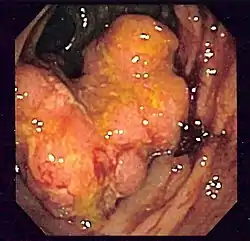

C'est une tumeur le plus souvent ulcérée à sa partie centrale, avec un bourgeonnement plus ou moins marqué en périphérie et une infiltration pariétale qui s'étend vers la séreuse ; elle est rarement végétante (cæcum). Elle occupe une partie ou la totalité de la circonférence colique[réf. nécessaire].

Apparence de l'intérieur d'un côlon développant un carcinome colorectal invasif (tumeur de forme irrégulière formant ici un cratère rougeâtre).